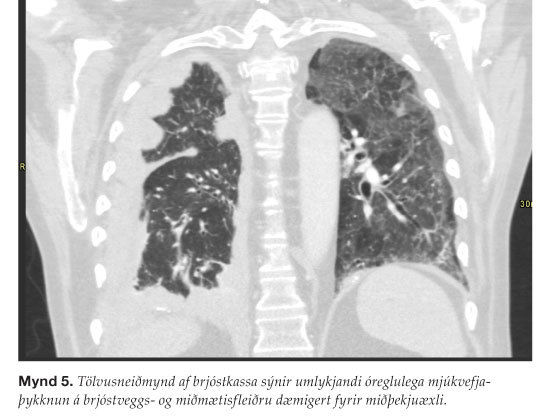

Miðþekjuæxli er krabbamein sem oftast kemur fyrir í lungna-fleiðru en getur þó myndast í öðrum himnum eins og lífhimnu og gollurshúsi.39,40 Þau hafa sterk tengsl við asbest þó aðrir orsakavaldar, svo sem ullarsteinn, séu einnig þekktir orsakavaldar. Biðtími frá asbestútsetningu og þar til æxli greinist er langur, allt að 20-50 ár.41,42 Einkenni eru ósértæk eins og brjóstverkur, hósti og nætursviti. Viðbótareinkenni geta komið fram við innvöxt í önnur líffæri. Miðþekjuæxli þekkist einnig hjá aðstandendum asb-estverkamanna sem komast í snertingu við asbestið með því að meðhöndla klæðnað þess sem vinnur við asbestið.41,42 Mynd 5 er af miðþekjuæxli í fleiðru. Þau greinast oftast með vefjasýni sem gjarna er tekið með nál sem stungið er milli rifja undir leiðsögn tölvusneiðmynda- eða ómtækis. Í öðrum tilvikum fæst greining með brjóstholsspeglun. Frumurannsókn á fleiðruvökva hefur ekki gott næmi til greiningar. Miðþekjuæxli hafa afar slæmar horfur og er lifun oft talin um 9-17 mánuðir. Meðferð beinist fyrst og fremst að því að draga úr einkennum, minnka verki og bæta lífsgæði. Til þess er beitt skurðaðgerðum, geislameðferð og frumudrepandi lyfj-um. Oftast eru notuð fleiri en eitt meðferðarform.43